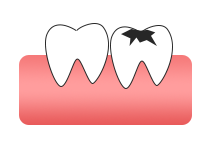

齲齒/蛀牙

兒童治齲——乳牙預成冠

Treatment of caries in children - precrown deciduous teeth乳牙預成冠是一個預先成型、與牙齒貼合的牙冠,套在乳牙上保護牙齒并增強其強度,确保乳牙正常健康的被恒牙替換,按照其牙位的實用(yòng)性,可(kě)分(fēn)為(wèi)樹脂預成冠(前牙)和金屬預成冠(後牙)。